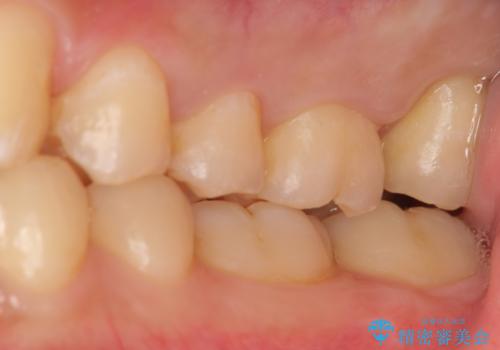

奥歯はすれ違ってしまっていました。

上顎両側7番(一番奥の歯)はすれ違っており、虫歯になっていました。